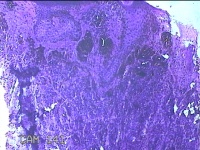

后颈部结节

性别

女

年龄

25岁

临床诊断

皮下结节

一般病史

发现后颈部“黑痣”20余年,伴近日局部瘙痒不适。

标本名称

大体所见

灰白粉红色带皮肤结节0.8x0.7x0.3cm一个,表面糜烂,切开结节呈实性,切面灰白粉红色,质软。

皮内痣